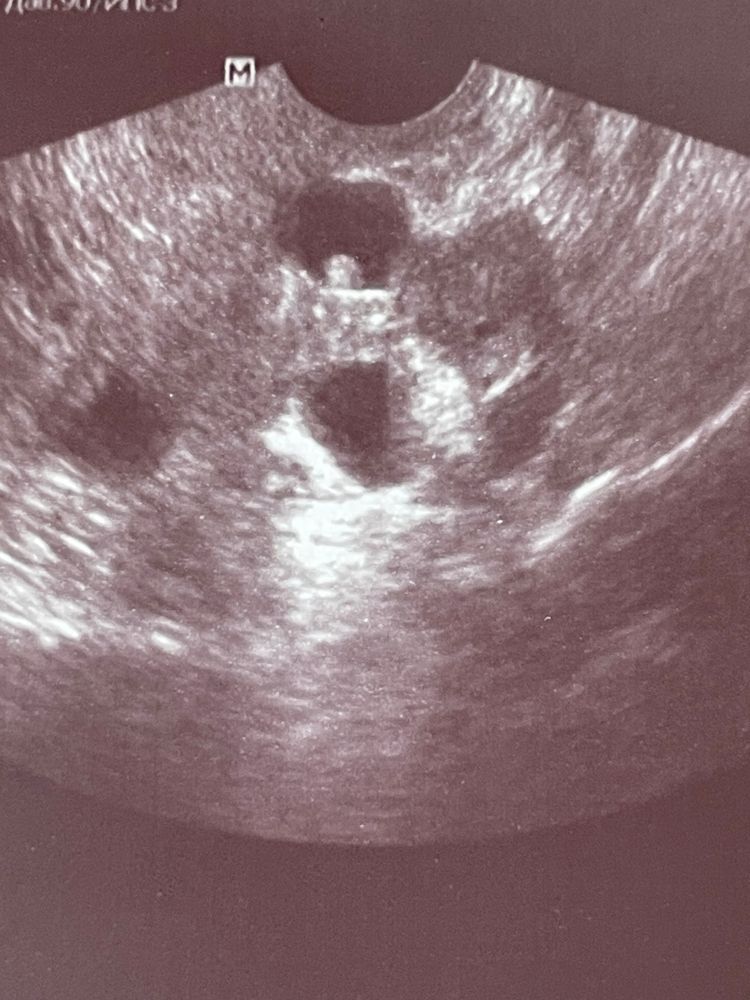

4 фото. Образование 19 мм, с пристеночный компонентом 3*4 мм - внематочная угловая беременность? (3 июня)